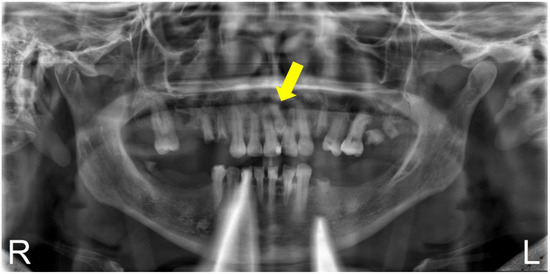

2.2. Case Report 2

| Case Report 2 | Female | Conoid mesiodens, included, vertical position, located between teeth 1.1 and 2.1 | 49 years old | Radiographic finding | Asymptomatic |